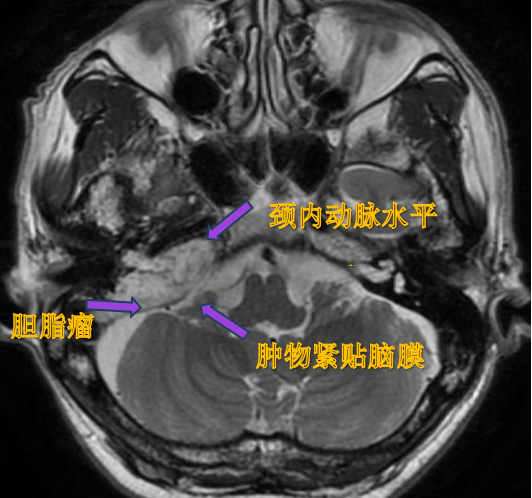

胆脂瘤破坏迷路骨质,并与脑膜紧贴

患者孙先生饱受面瘫之苦三十多年,起初通过针灸缓解,后来面瘫反复发作,不仅针灸治疗不再理想,还出现了平衡障碍、眩晕和全聋。经多方询问,他来到北京清华长庚医院耳鼻咽喉头颈外科眩晕专病中心,结合临床经验,主任医师伊海金为他安排了颞骨CT检查和增强颅底核磁检查,结果显示导致面瘫的“真凶”是岩骨胆脂瘤。由于患病时间长,胆脂瘤不仅破坏了三大神经,侵犯了中、后颅窝,还破坏了颅底颈内动、静脉周围的骨质,胆脂瘤与脑膜和颈内动、静脉紧紧相贴,若再不及时处理,可能会出现颅内感染及血管破裂等严重并发症。